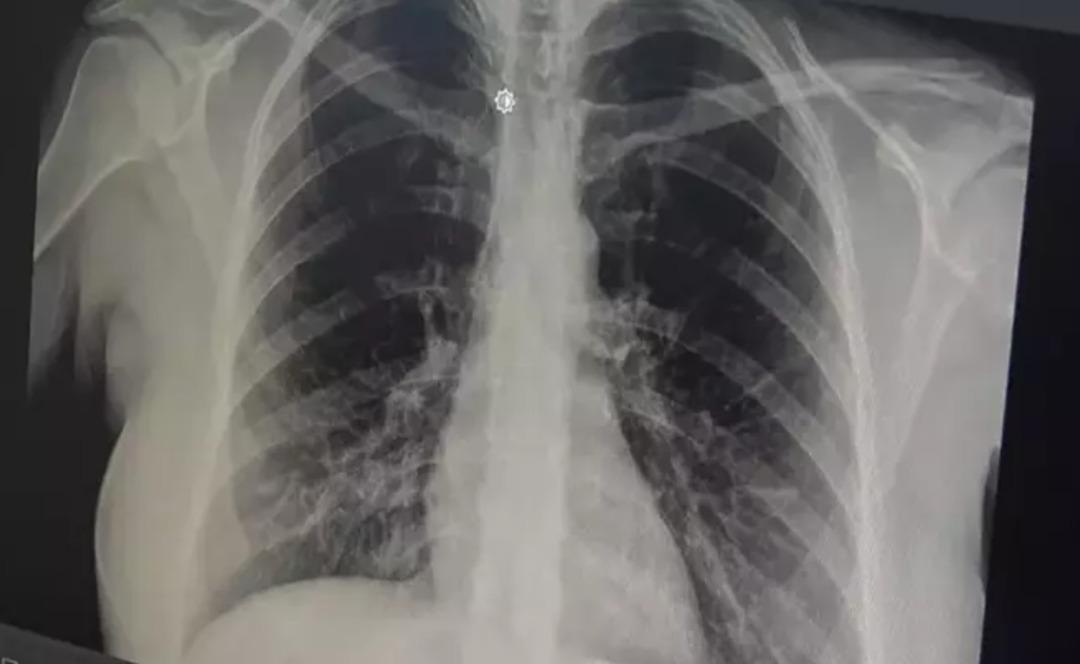

Göğüs Hastalıkları Uzmanı Prof. Dr. Tevfik Özlü, akut bronşitin giderek yayıldığına dikkat çekerek önerilerde bulundu. prof. Akut bronşitin ilk belirtilerinin boğaz ağrısı, hafif ateş ve burun akıntısı olduğunu ancak enfeksiyon bronşlara yayıldığında göğüs ağrısı ve şiddetli öksürüğün ortaya çıktığını söyleyen Dr. Özlü, akut bronşitin hafif ve tedavi edilebilir bir hastalık olduğunu belirterek, hastaların doktora başvurması konusunda uyardı.

prof. Akut bronşitin solunum yolu virüslerinin neden olduğu bir hastalık olduğunu belirten Dr. Özlü, şöyle konuştu: “Günümüzde çok sık gördüğümüz bir hastalık. Genelde hastalar şöyle tarif ediyor: 'Öncelikle boğazım ağrıyordu, boğazım ağrıyordu. hafif ateş, burun akıntısı, hapşırma, geniz akıntısı ve öksürük: “2-3 gündür göğsümdeydi. Nefes alırken acı hissediyorum. İçeride bir çalı varmış gibi görünüyor. Nefes aldığımda göğsüm oraya sıkışıyor” çünkü aslında gerçek bu. “Bronşit, solunum yolu virüslerinin neden olduğu bulaşıcı bir hastalıktır. Bu enfeksiyon üst solunum yollarıyla sınırlı olmayıp alt solunum yolları ve bronşları da etkiliyor” dedi.

Akut bronşitin en önemli belirtisinin öksürük olduğunu vurgulayan Prof. Dr. Tevfik Özlü, “Kuru öksürük veya balgamlı öksürük şeklinde kendini gösterebiliyor. Bazen belirti daha çok hırıltılı solunum ve nefes darlığı şeklinde hissedilebiliyor. Yüksek ateş genellikle herhangi bir rahatsızlığa neden olmaz ancak bazen bakteriyel enfeksiyonlar da ortaya çıkabilir” dedi.

Bronşitin genel olarak hafif bir hastalık olduğunu ancak belirtilerin artması durumunda doktora başvurulması gerektiğini belirten Özlü, şöyle konuştu: “Altta yatan kronik bir hastalık, astım veya KOAH obstrüktif hastalığı gibi bir akciğer hastalığı varsa, kronik hastalığın akut alevlenmesidir. buna hastalık eşlik edebilir ve genel akut bronşit nefes darlığı, hırıltılı solunum, halsizlik, yorgunluk ve yüksek ateş gibi ciddi belirtilerle ortaya çıkabilir veya altta yatan kronik bir hastalık varsa ve belirtilerde alevlenme varsa mutlaka doktora görünün” Genel olarak hafif ve tedavi edilebilir bir hastalık olduğunu söyleyebilirim” dedi.